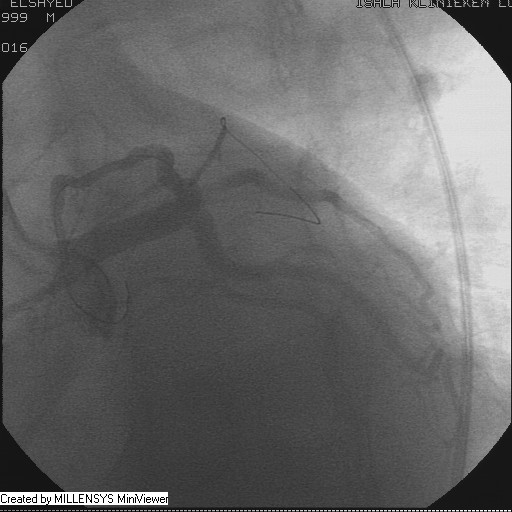

After crossing with the PTCA wire, a minimal flow started to appear in the diagonal branch (Figure 6), then LAD was wired, then a 2x15mm Balloon was used to pre-dilate (Figure 7,8), a big diagonal branch appeared with proximal thrombotic tight lesion (Figure 9), the diagonal angle to LAD was about 90 degree (Figure 10), so provisional stenting done to diagonal from its ostium with 3x20mm PROMUS ELEMENT PLUS DES (Figure 11,12), with good final result (Figures 13&14).

Figure 13

Figure 14